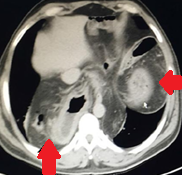

Αμφοτερόπλευρη αυτόματη νεφρική αιμορραγία — κοκκιωμάτωση Wegener (Ευγενική παραχώρηση Dr. V. Penopoulos)